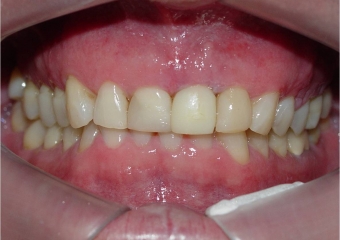

Mordida com prótese provisória fixa sobre implante

Sorriso final